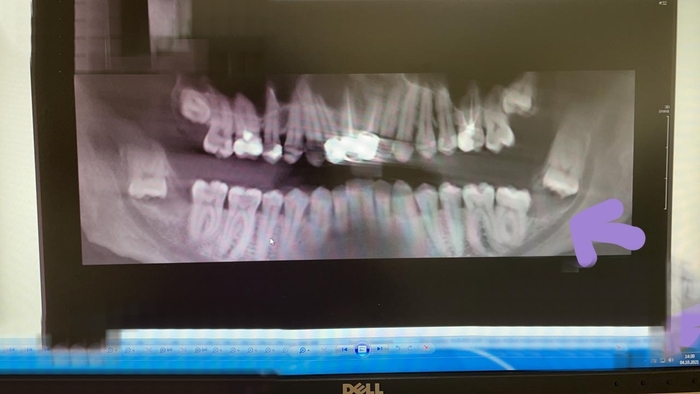

О том что мои верхние восьмёрки нужно удалять я знаю уже пять лет, об этом мне сказали в частной стоматологии, где я лечила зубы. Восьмерки эти в кариесе, который нельзя запломбировать, так как бор машиной туда не подлезть.

Поняв что ситуация выходит из под контроля зашла на консультацию к стоматологу, где мне и сказали что зубы у меня в порядке, только нужно срочно удалять верхние пульпитные восьмёрки и вероятно именно они отдают болью по всей челюсти.